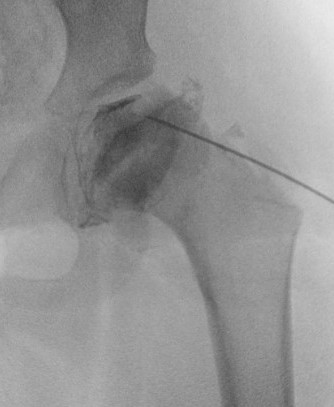

US

Nonspecific findings of synovitis usually found

- thickening synovial membrane vs. synovitis

- synovial effusion

CT

MRI

Advantage

- can assess amount of cartilaginous head outside of acetabulum

- very good way of assessing containment of cartilage head